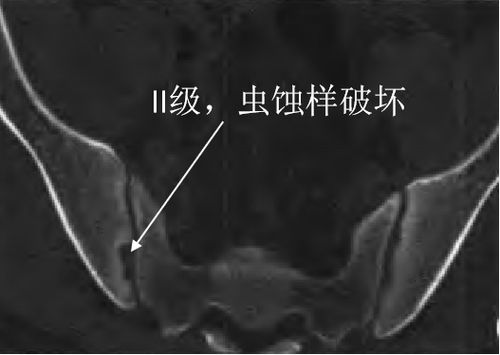

骶髂关节炎ct

骶髂关节炎ct,骶髂关节炎的症状

骶髂关节炎:x线,ct和mri表现

骶髂关节炎ct图像表现